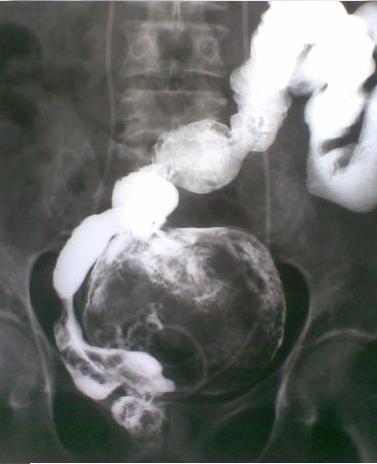

Image de lavement baryte en double de contrast :

Tuberculose ileo-caecale avec image de ileon tres

deforme , bord irregulier , angulation et stenosante

. |

Tuberculose ileo-caecale : image de

deformation en conique du caecum . Ileon est

irregulie et stenosante . Image de lavement baryte

mono de contrast . |